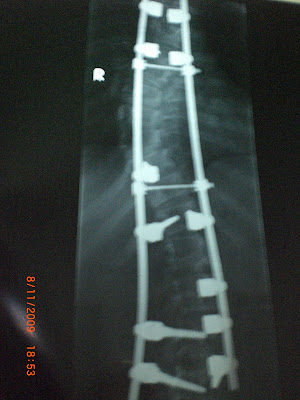

The curve became more serious. In 2006, I had a surgery.

Surgery is usually required with a curve of 40 to 50 degrees but I waited until 80 degrees because once the surgery is done the height is 80 to 90 percent fixed.So, I waited after the puberty.

The surgery involves a combination of rods, screws, human made bones and wires fixing the spine and can apply stronger, safer forces to the spine than the Harrington rod. This technique is known as the Cotrel-Dubousset instrumentation, currently the most common technique for the procedure.

***** after surgery *****

NOW...

MARCH 2006